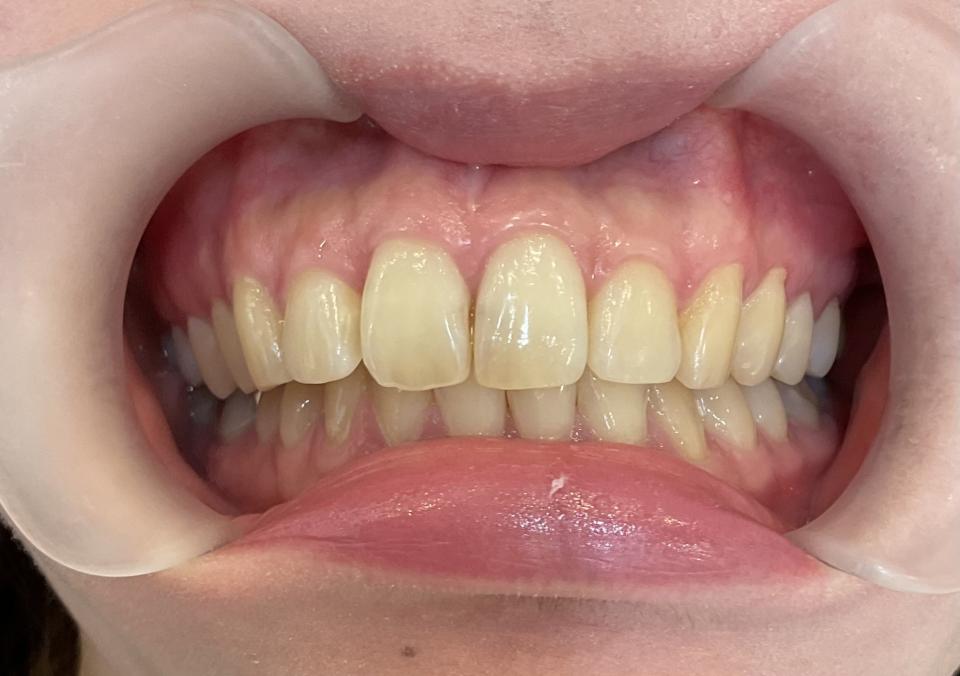

矯正治療後

現在はマウスピース型のリテーナーで後戻りの防止をして定期的にチェックをしています。

| 矯正治療期間 | 7か月 |

| 抜歯の有無 | なし |

| 治療費 | 300000円(検査/診断/施術料含む) |